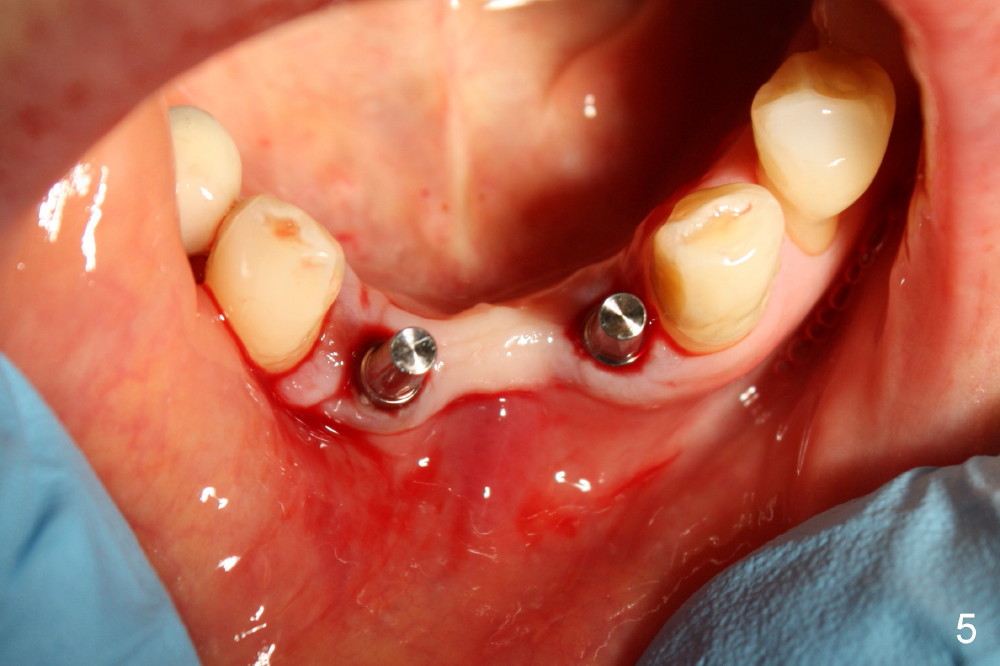

Two of one piece implants (3x17 mm) were placed at the sites of #23 and 26 on February 13, 2013 (Fig.5). The implant at the site of #26 was placed a little too labially with possible coronal labial plate fracture. Immediately fabricated was a provisional FPD, which was replaced by a definitive one three months and a half later (Fig.7).  PA in Fig.6 is taken five months post implantation (I: one-piece implant).